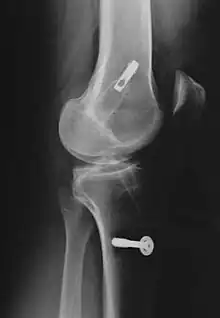

| Arthroscopic anterior cruciate ligament (ACL) reconstruction (right knee). The tendon of the semitendinosus muscle was prelevated, folded and used as an autograft (1). It appears through the remnant of the injured original ACL (3). The autograft then courses upwardly and backwardly in front of the posterior cruciate ligament (2). | |